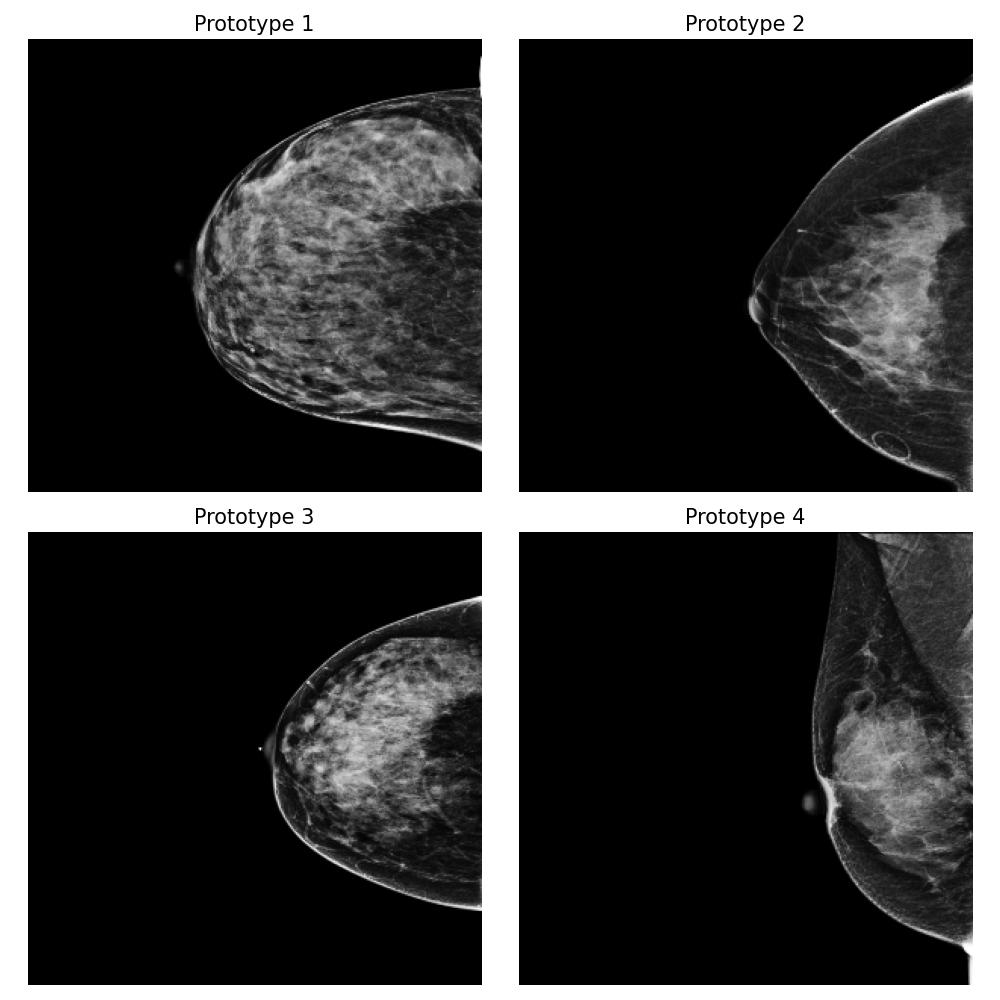

Dataset and

We use the publicly available EMBED dataset (Jeong et al., 2023). To simulate premenopausal and postmenopausal patient populations, we construct two datasets, and , by randomly sub-sampling from EMBED. Dataset comprises 27,224 mammograms from 8,456 patients with dense breast tissue (density category three in EMBED) and 21,675 mammograms from 7,841 patients in density category two. Dataset includes 27,224 mammograms from 2,715 patients with less dense tissue (density category one) and 21,675 mammograms from 7,797 patients in density category two (medium density). All mammograms were preprocessed to remove clinical markers and aligned such that the breast tissue faces left.

For this task, we implemented the “Prototype-summarization-based explanations” described in Section 3.5. We trained a binary vs classifier using the VGG19 feature extractor as backbone and learn four prototypes for each dataset. 97798 mammograms were used for training, and 24450 mammograms were used for testing.

Result

By examining the summarization prototypes shown in Figure 22, we identified tissue density as the primary difference between and . In mammograms, brighter areas correspond to denser tissue. Additionally, we observed that less dense tissue is often associated with larger tissue size. Without our proposed method, human users would need to manually analyze the dataset, which is a labor-intensive and time-consuming task, to reach the same conclusions.

Robustness of the explanation

To examine the robustness of our explanation result, we repeat the explanation algorithm approach on bootstrapped versions of and . Five bootstrapped datasets were constructed by resampling by patients with replacement. As shown in Figure 35 in Appendix Section B.5, we reach the same conclusion for all the bootstrapped datasets.

Coverage evaluation

We again evaluate the coverage quality of the learned set of prototypes using the AUCC score. The coverage curve is shown in Figure 24. We also display the learned latent space for and in Figure 24 and the two datasets and the prototypes are well separated even though they contain overlapping mammograms with density category two (i.e. medium density breasts).